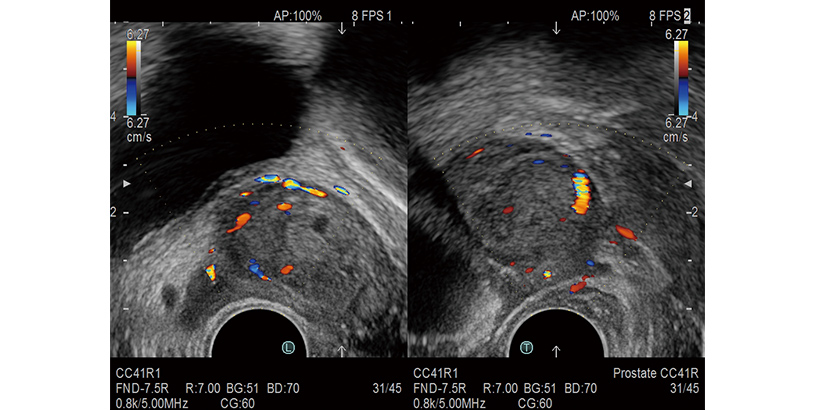

It is possible to display short and long axis images of the prostate side by side in real time.

Courtesy of : Dr. Sunao Shoji, Department of Urology, Tokai University School of Medicine